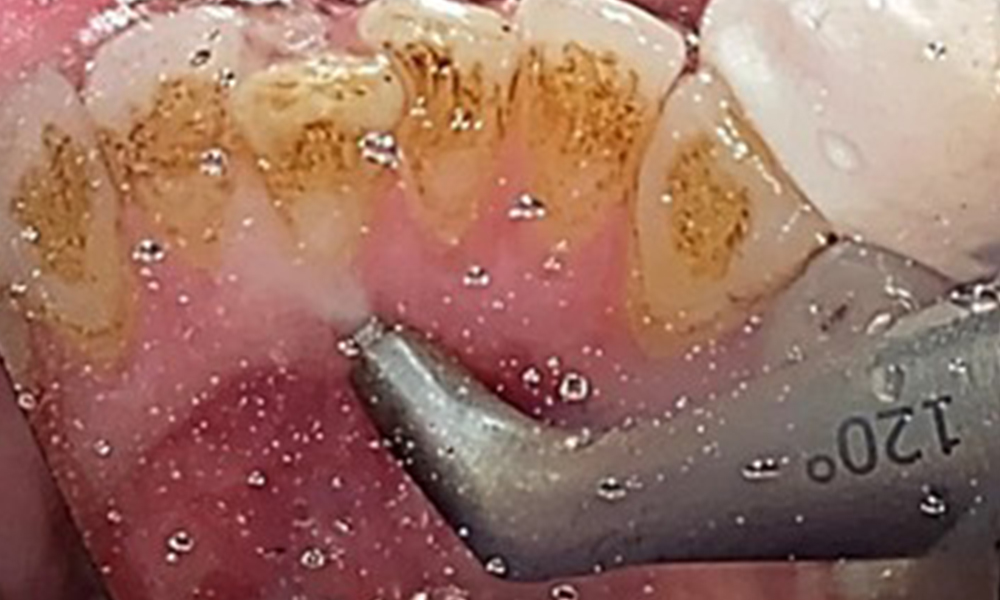

L'objectif serait de contrôler le risque de maladie en éliminant le biofilm supra-gingival et sous-gingival. Les instruments peuvent être sélectionnés en fonction des besoins du patient. Tout d'abord, le tartre et les concrétions doivent être éliminés à l'aide d'instruments ultrasoniques et/ou manuels (Fig. 10).

Utilisation d'un appareil à ultrasons piézoélectrique dans la zone linguale près de 36 (Proxeo Ultra, W&H, illustré ici).

Fig. 10 Utilisation d'un appareil à ultrasons piézoélectrique dans la zone linguale près de 36 (Proxeo Ultra, W&H, illustré ici)., © Dr R. Krapf